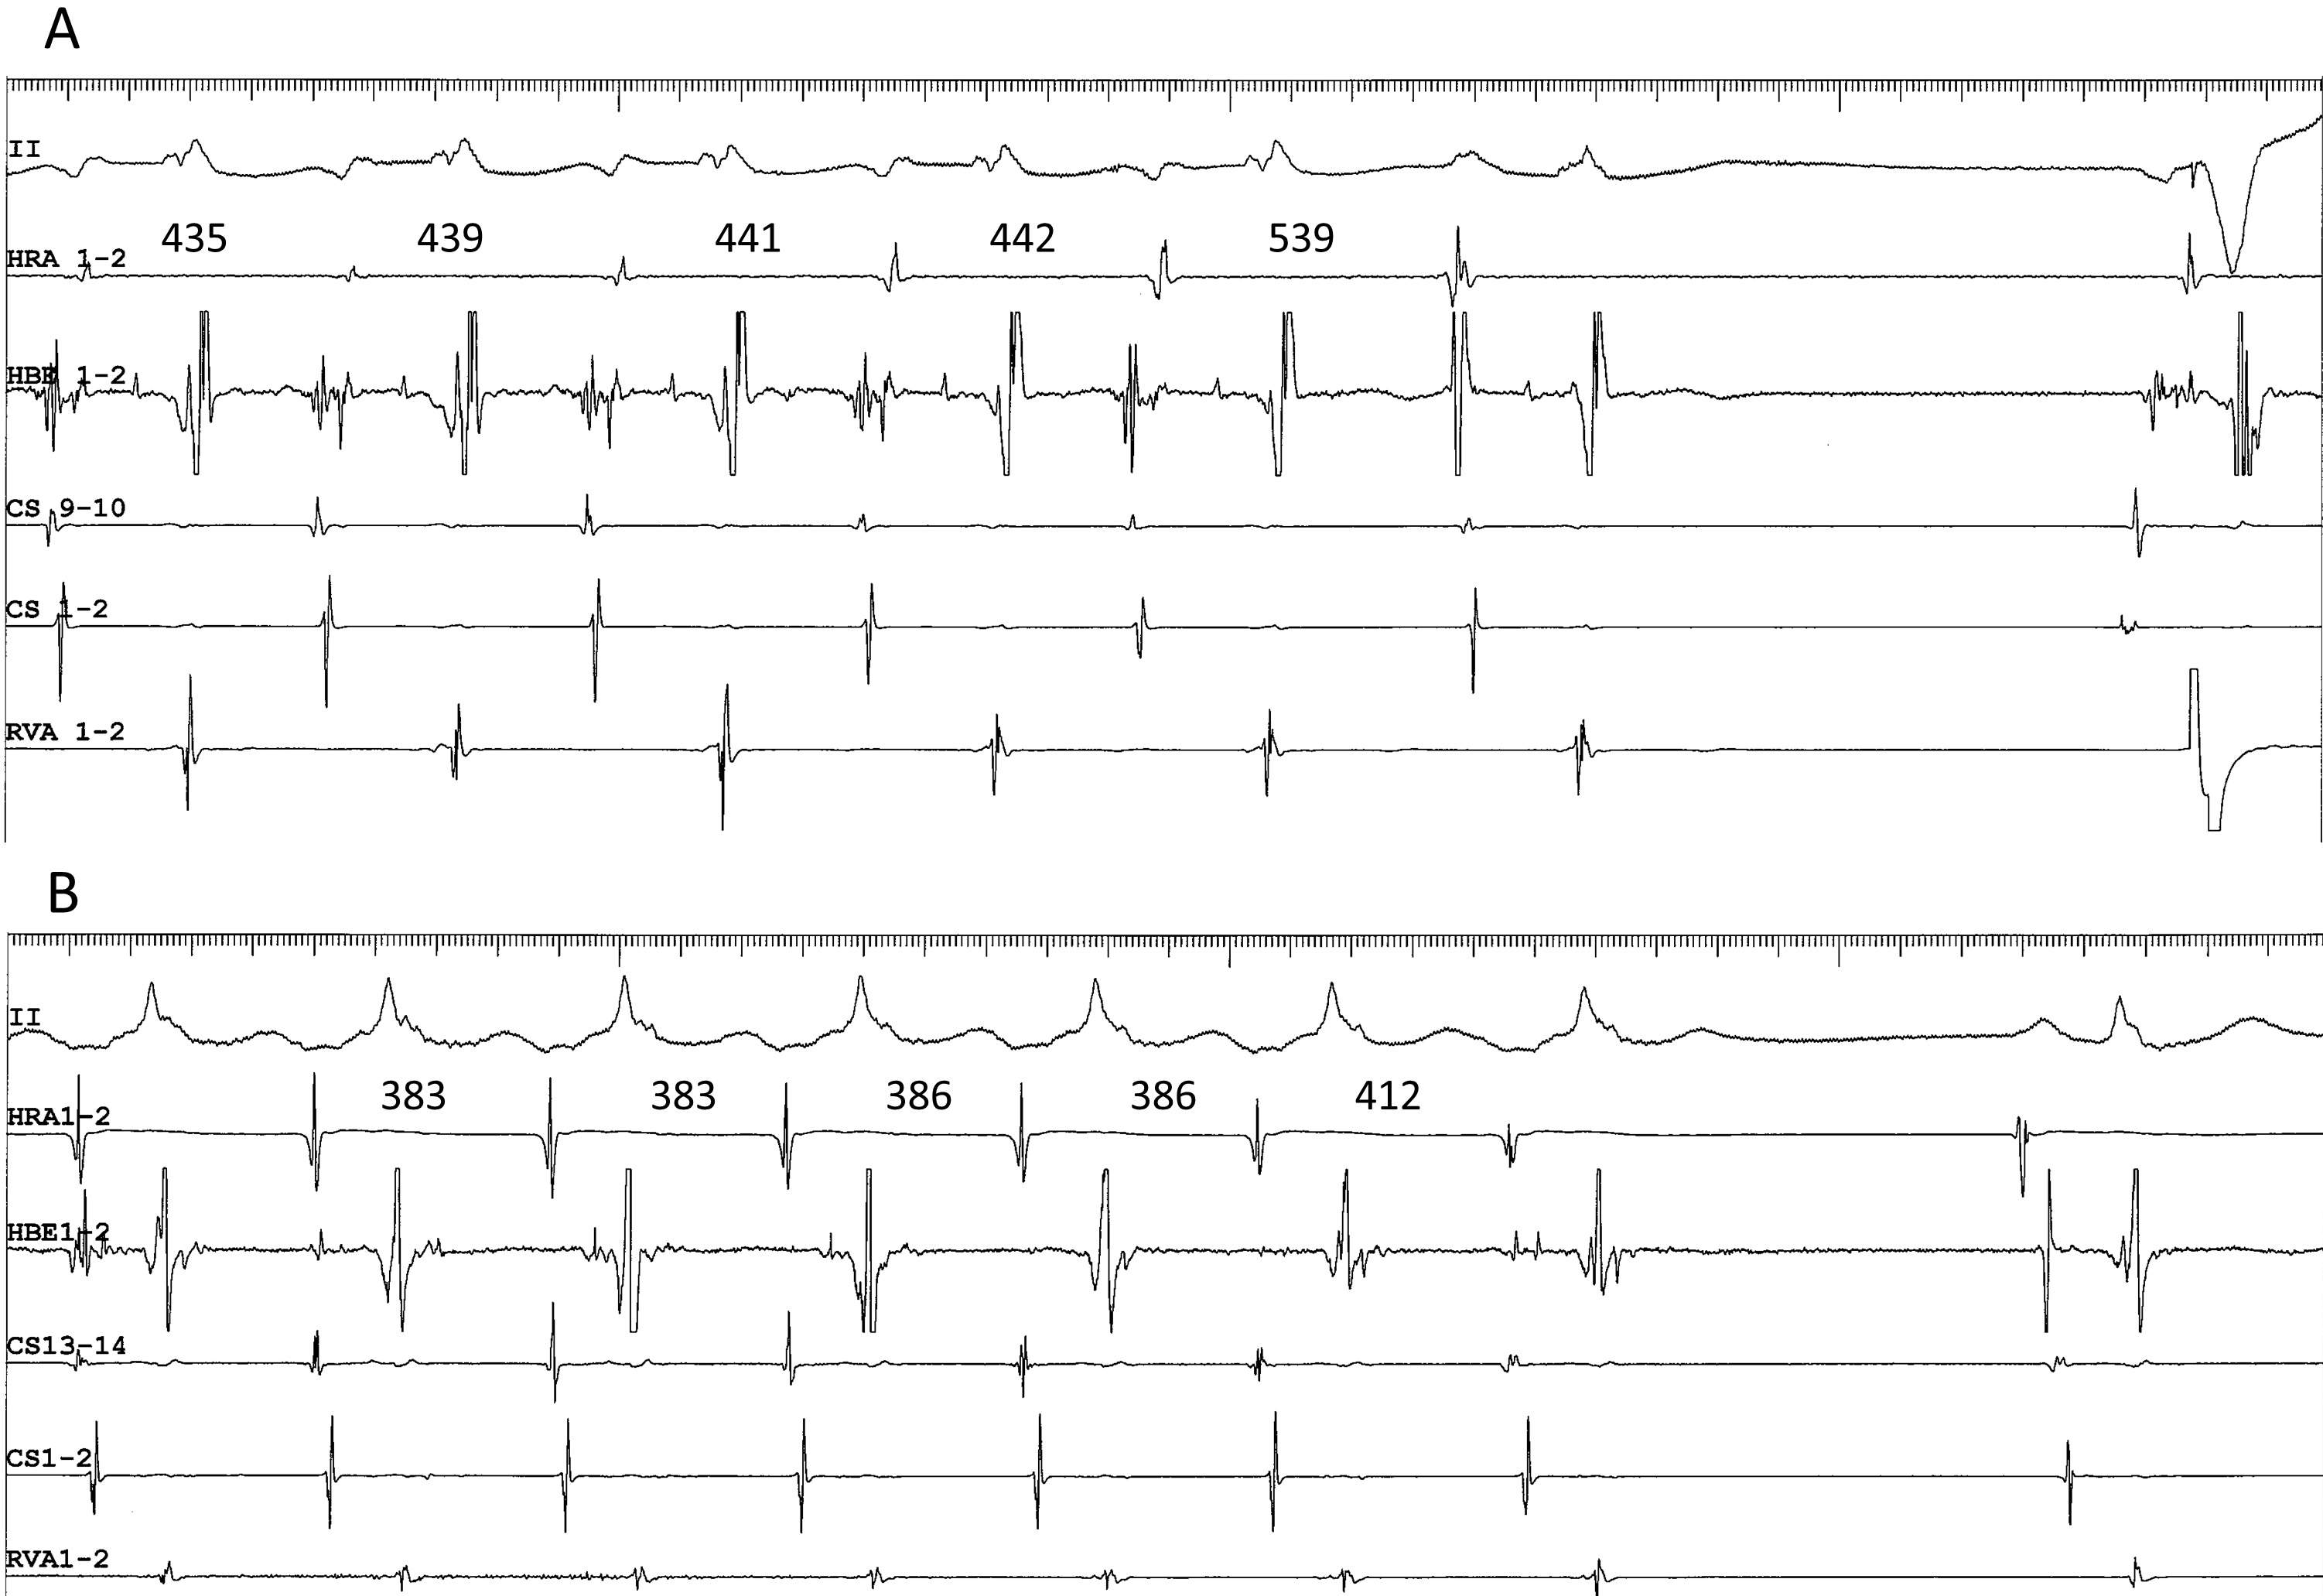

Fig. 5.Differential atrial entrainment pacing at an S-S cycle length of 365 ms from the high right atrium (HRA1-2) (A) and the proximal coronary sinus (CS9-10) (B), in a patient presenting with fast-slow AVNRT using an inferolateral, right atrial SP. This patient is the same as in Fig. 4D. Note: (1) the atypical atrial activation sequence during tachycardia, characterized by nearly simultaneous atrial electrograms in the HRA and in the His bundle region (HBE1-2); and (2) shorter His-atrial intervals immediately after entrainment pacing (indicated by horizontal bidirectional arrows and numbers above) in the HRA than in the proximal coronary sinus (CS9-10). II, surface electrocardiogram lead II; CS13-14 to 1-2, proximal to distal coronary sinus; RVA, right ventricular apex.

We present a unique response to differential atrial entrainment pacing of inferolateral fast-slow AVNRT. Differential atrial entrainment pacing of typical fast-slow AVNRT may reveal the absence of VA linking, characterized by a shorter VA interval after pacing from the proximal CS than from the HRA, due to the pacing site-dependent effect described earlier [35]. In contrast, differential atrial entrainment pacing of inferolateral, fast-slow AVNRT may reproducibly reveal a reverse relationship of the VA interval, characterized by a shorter VA interval after pacing from the HRA than from the proximal CS (Fig. 5). This may be due to the atypical location of the atrial end of the SP, relatively away from the proximal CS and closer to the HRA, causing a deeper penetration into the SP during pacing from the HRA than from the proximal CS. The subsequent retrograde conduction time over the SP is, therefore, shorter after pacing from the HRA than from the proximal CS. This information may be helpful when interpreting the results from differential atrial entrainment pacing of fast-slow AVNRT.